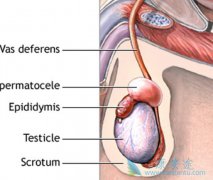

睾丸癌的病因至今还不十分明确,有可能与睾丸外伤、感染后发生癌变有关。也有学者认为,睾丸肿瘤的发病与遗传因素、环境因素、内分泌异常等因素相关,而可以肯定的是,隐睾是睾丸癌变的原因之一。男性隐睾,睾丸长期在腹腔里受高温烘焙,容易发生癌变。 ...

睾丸癌占男性癌症病例的1%。高个男性也不必因为这项研究结果而感到恐慌,因为只有不到4%的睾丸结块属于睾丸癌。但是由于睾丸癌在25―34岁男性中最多,所以年轻男性一旦发现睾丸异常,应该立即就医,查明真相。以下四大信号可能是 睾丸癌症状 。睾丸肿大 ...